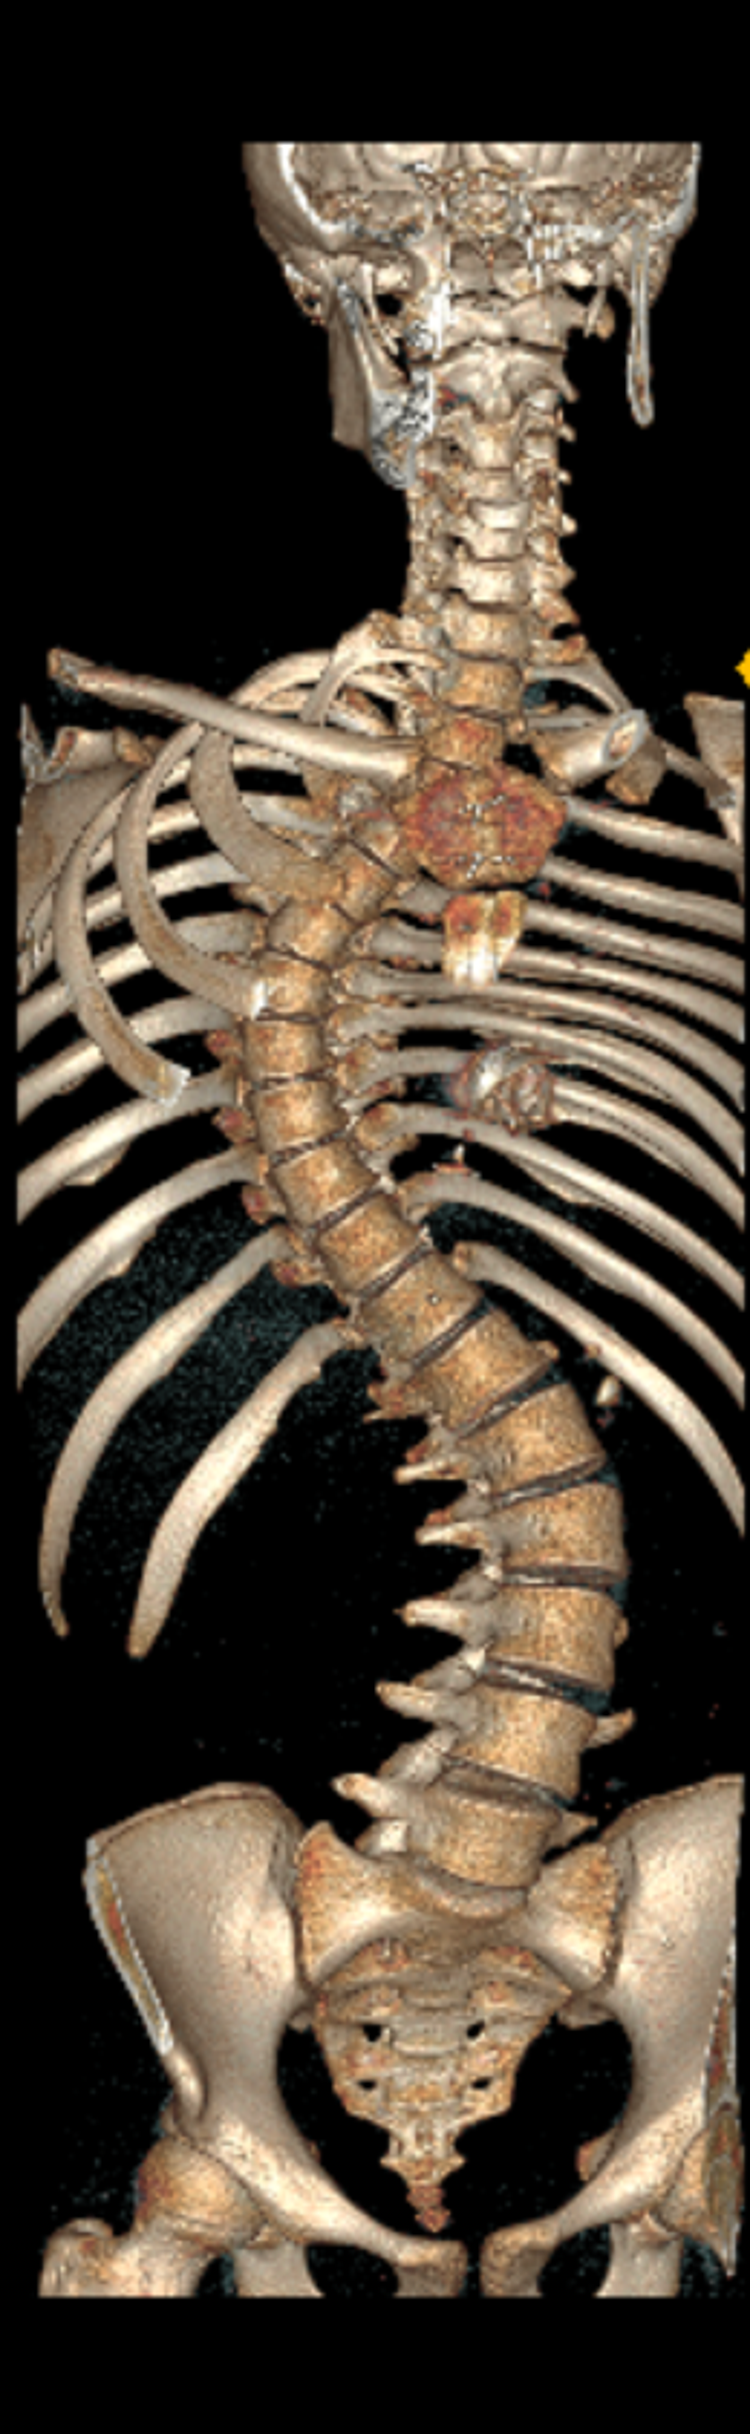

Eren'in sırt bölgesinde 90, bel bölgesinde 70 dereceye ulaşan eğrilik tespit edildi. Eren, kalp kapağı ameliyatı nedeniyle kullandığı kan sulandırıcı ilaçlar kesilmeden biri 8 saat, diğeri 6 saat olmak üzere 2 seanslık riskli operasyonla skolyozdan kurtuldu. Eren, yüksek miktarda kan kaybı yaşamasına rağmen başarılı geçen operasyonun ardından sağlığına kavuştu.